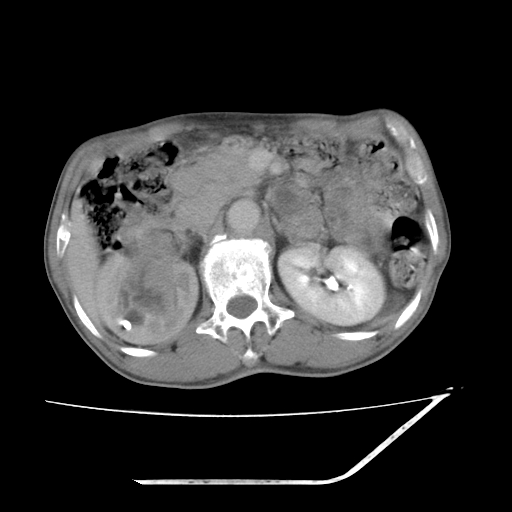

增强

考虑右肾盂癌,肾动脉受侵,右肾功能减退,右肾盂输尿管积水,管壁增厚,考虑种植转移,应该把下面扫完的

支持右侧肾盂癌伴肾静脉瘤栓形成可能性大,右肾结石.肝右叶后段低密度影,不除外转移.

右肾盂旁ca并肾静脉瘤栓形成/肾功能降低。

右肾结石。

右肾盂癌,肾动脉受侵,右肾盂输尿管积水,管壁增厚,考虑种植转移

支持 右侧肾盂癌伴肾静脉瘤栓形成可能性大,右肾结石;肝右叶后段低密度影,不除外转移。

1.右侧肾盂癌伴肾盂积水。

2.肾脏功能减退,原因有:(1)肾动脉受侵。(2)肾静脉受侵(3)肾积水,等。本例,肾动脉显影较好,但受压明显;肾静脉无明显显示,受压或静脉癌栓,下腔静脉腔内未见明显充盈缺损。

3.右侧上段输尿管扩张,原因:(1)积水所致;(2)种植。